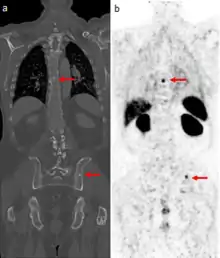

A gallium scan is a type of nuclear medicine test that uses either a gallium-67 (67Ga) or gallium-68 (68Ga) radiopharmaceutical to obtain images of a specific type of tissue, or disease state of tissue. Gallium salts like gallium citrate and gallium nitrate may be used. The form of salt is not important, since it is the freely dissolved gallium ion Ga3+ which is active.[1] Both 67Ga and 68Ga salts have similar uptake mechanisms.[2] Gallium can also be used in other forms, for example 68Ga-PSMA is used for cancer imaging. The gamma emission of gallium-67 is imaged by a gamma camera, while the positron emission of gallium-68 is imaged by positron emission tomography (PET).

Gallium salts are taken up by tumors, inflammation, and both acute and chronic infection,[3][4] allowing these pathological processes to be imaged. Gallium is particularly useful in imaging osteomyelitis that involves the spine, and in imaging older and chronic infections that may be the cause of a fever of unknown origin.[5][6]

Gallium-68 DOTA scans are increasingly replacing octreotide scans (a type of indium-111 scan using octreotide as a somatostatin receptor ligand). The gallium-68 is bound to an octreotide derivative chemical such as DOTATOC and the positrons it emits are imaged by PET-CT scan. Such scans are useful in locating neuroendocrine tumors and pancreatic cancer.[7][8]

In the past, the gallium scan was the gold standard for lymphoma staging, until it was replaced by positron emission tomography (PET) using fludeoxyglucose (FDG).[9][10] Gallium imaging is still used to image inflammation and chronic infections, and it still sometimes locates unsuspected tumors as it is taken up by many kinds of cancer cells in amounts that exceed those of normal tissues. Thus, an increased uptake of gallium-67 may indicate a new or old infection, an inflammatory focus from any cause, or a cancerous tumor.

Gallium DOTA scans

68Ga DOTA conjugated peptides (including 68Ga DOTA-TATE, DOTA-TOC and DOTA-NOC) are used in positron emission tomography (PET) imaging of neuroendocrine tumours (NETs). The scan is similar to the SPECT octreotide scan in that an octreotide-based somatostatin analogue (such as edotreotide) is used as the radioligand, and there are similar indications and uses as ocreotide scans, however image quality is significantly improved.[35] Somatostatin receptors are overexpressed in many NETs, so that the 68Ga DOTA conjugated peptide is preferentially taken up in these locations, and visualised on the scan.[36] As well as diagnosis and staging of NETs, 68Ga DOTA conjugated peptide imaging may be used for planning and dosimetry in preparation for lutetium-177 or yttrium-90 DOTA therapy.[37][38]